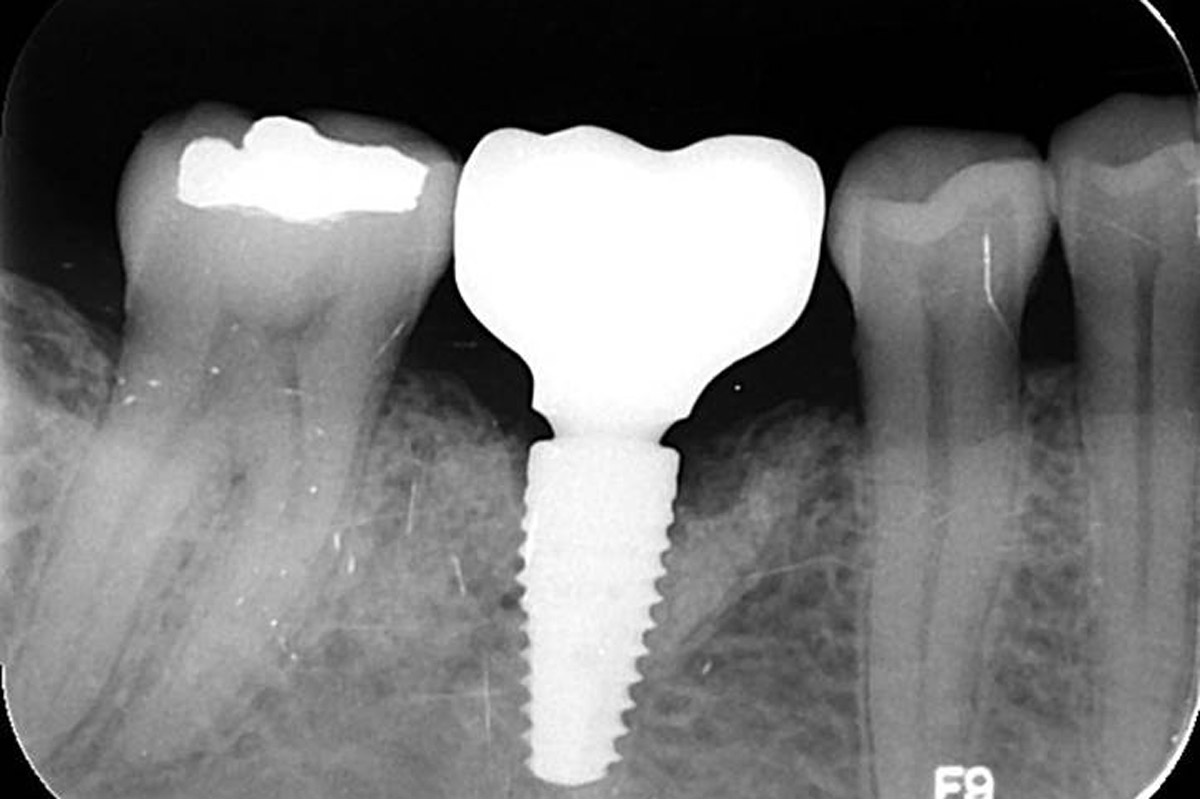

Pre-operative OPG, teeth 24, 25, and 26 planned for extraction